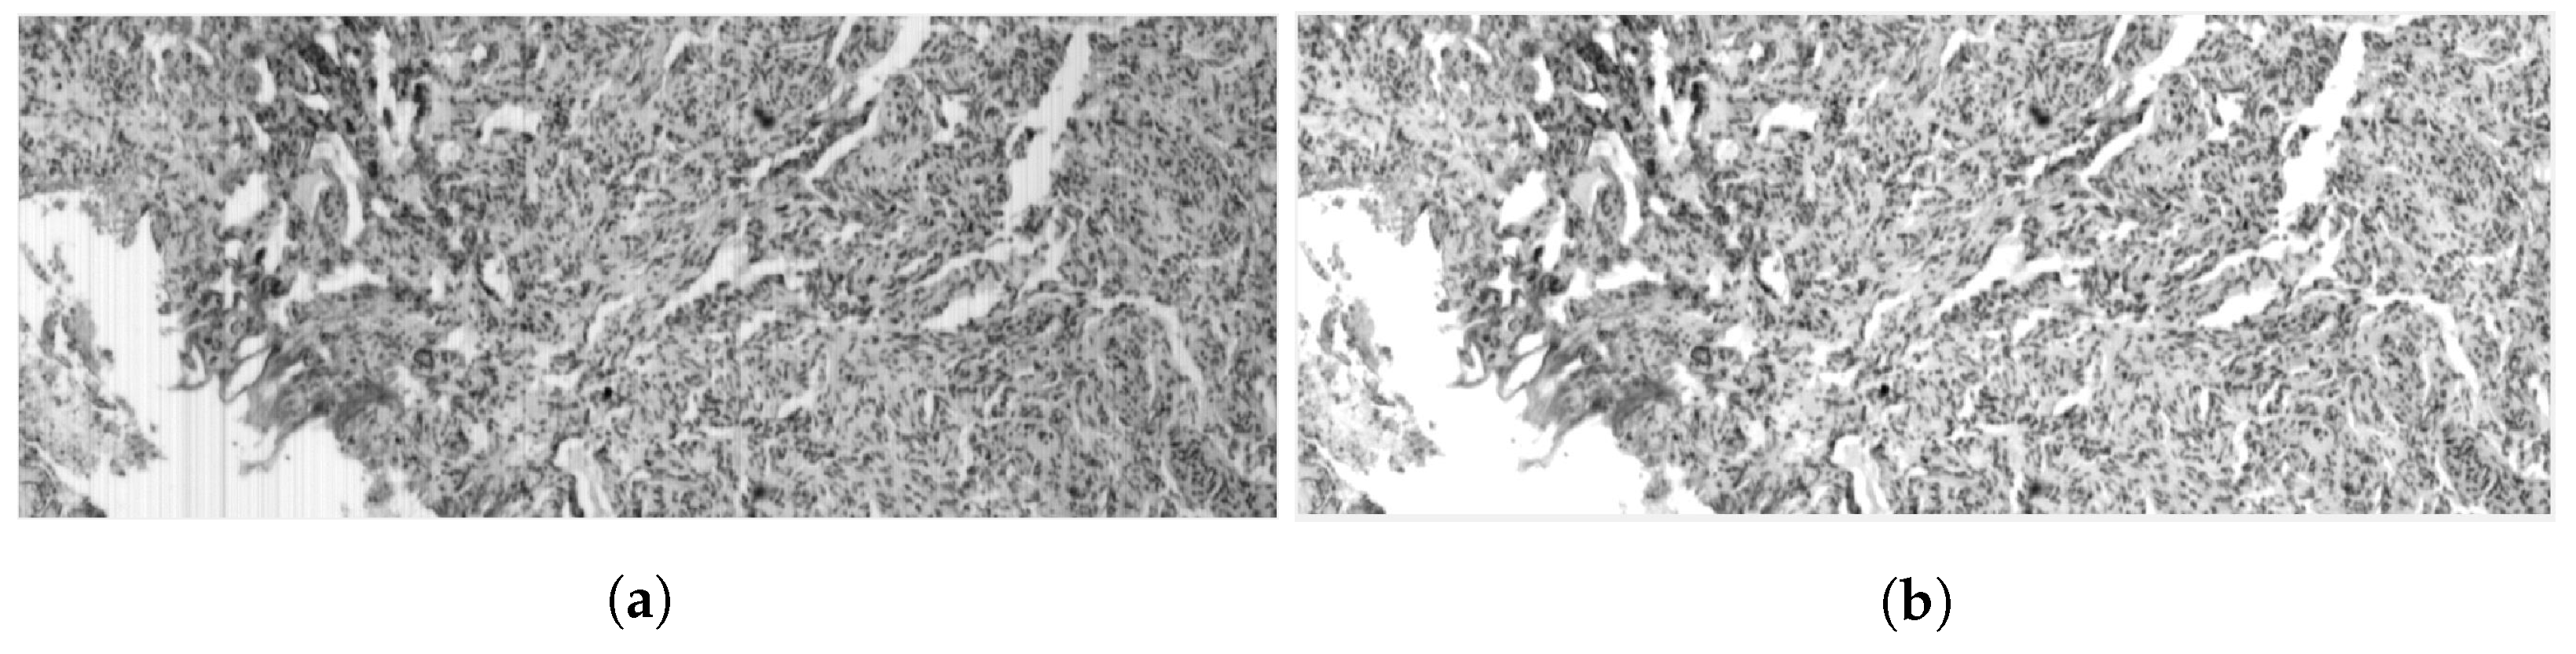

3.3. Sequence 3—High Background Content Brain Tissue

3.4. Sequence 4—Brain Tissue with Small Objects

3.5. Sequence 5—Highly-Granular Brain Tissue

4. Discussion